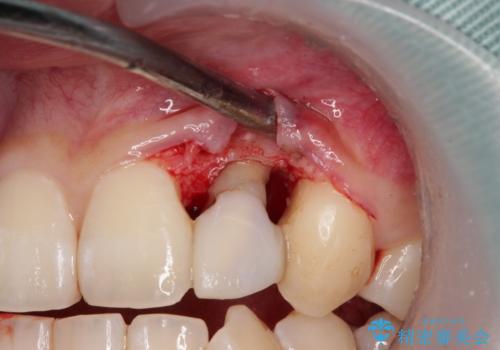

過去にぶつけたことで神経組織が壊死してしまったようで、その後むし歯が進行して歯肉深いところにまで進んでいる状態でした。

まずは部分矯正により歯を牽引し、歯肉や歯槽骨の位置を調整するために歯周外科処置を行い、治癒を待ってオールセラミッククラウンにて補綴治療を行うこととしました。